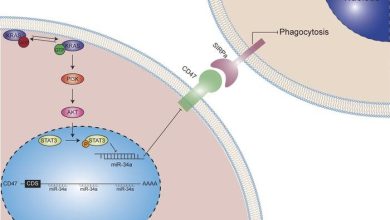

Mutação KRAS mostrou promover a evasão tumoral da vigilância imune inata no câncer de pulmão

Resumo gráfico. Crédito: Jornal de Investigação Clínica (2022). DOI: 10.1172/JCI153470 KRAS é um dos oncogenes mais freqüentemente ativados em cânceres…